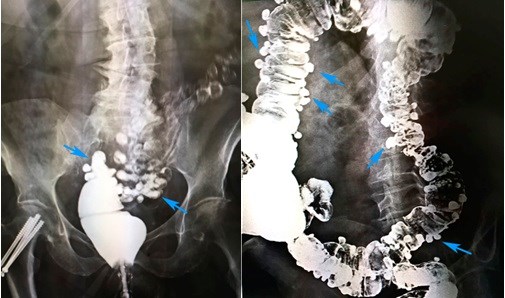

«Золотым стандартом» диагностики дивертикулярной болезни является ирригоскопия. Этот метод позволяет определить количество дивертикулов, их точное местоположение, размеры и форму. Суть процедуры заключается в введении рентгенконтрастного препарата в толстую кишку, после этого выполняется серия рентгенологических снимков, позволяющих оценить состояние толстой кишки. На представленных фотографиях стрелками указаны устья дивертикулов толстой кишки. Синими стрелками мы отметили множественные дивертикулы ободочной кишки. Именно так они выглядят при компьютерной томографии.

Ирригоскопия. Дивертикулез толстой кишки

На рентгенологических снимках, выполненных при ирригоскопическом исследовании, отчетливо видны множественные дивертикулы ободочной кишки. Они выглядят как мешочки, заполненные рентгеноконтрастным препаратом.